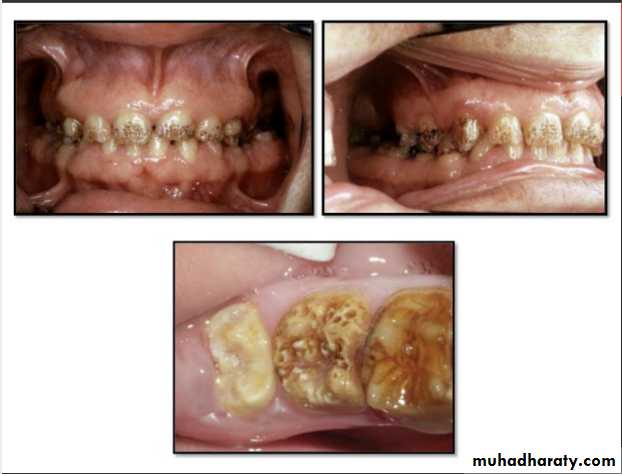

Amelogenesis Imperfecta

*It is a developmental disturbance that interferes with normal enamel formation.*It leads to marked changes in the enamel of all or nearly all the teeth in both dentitions.

Hypoplastic Amelogenesis Imperfecta:

* Due to some defect in ameloblasts enamel fails to develop to its normal thickness dentin exposed the tooth shows yellowish-brown color.*Enamel is randomly:

pitted .

rough OR smooth &glossy.

*The occlusal surfaces of the posterior teeth are relatively

flat with low cusps due to attrition of cusp tips that were initially low and not fully formed. An anterior open bite may be noted. defects become stained but teeth are not especially susceptible to caries unless enamel is scanty and easily damaged.

Generalized hypoplastic type

Amelogenesis ImperfectaAffects primary &permenant dentition

Severe mottling of the enamel surface.